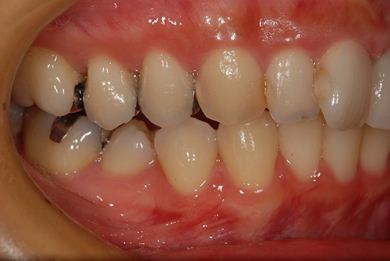

| 性別/年齢 | 女性 / 31歳 | ||||||||||||||||||||||||||||||||

| 主訴 | 前歯の歯茎が黒ずんでいるので、改善したい。 | ||||||||||||||||||||||||||||||||

| 治療方針 | 上顎前歯、メタルボンドセラミッククラウンからオールセラミッククラウンにする事で、審美的回復を行う。 | ||||||||||||||||||||||||||||||||

| 治療内容 | CAD/CAMオールセラミッククラウン2本(セラミック用土台2本) | ||||||||||||||||||||||||||||||||

| 総治療費 | 142,800円 | ||||||||||||||||||||||||||||||||

| 治療期間 | 2ヶ月 |